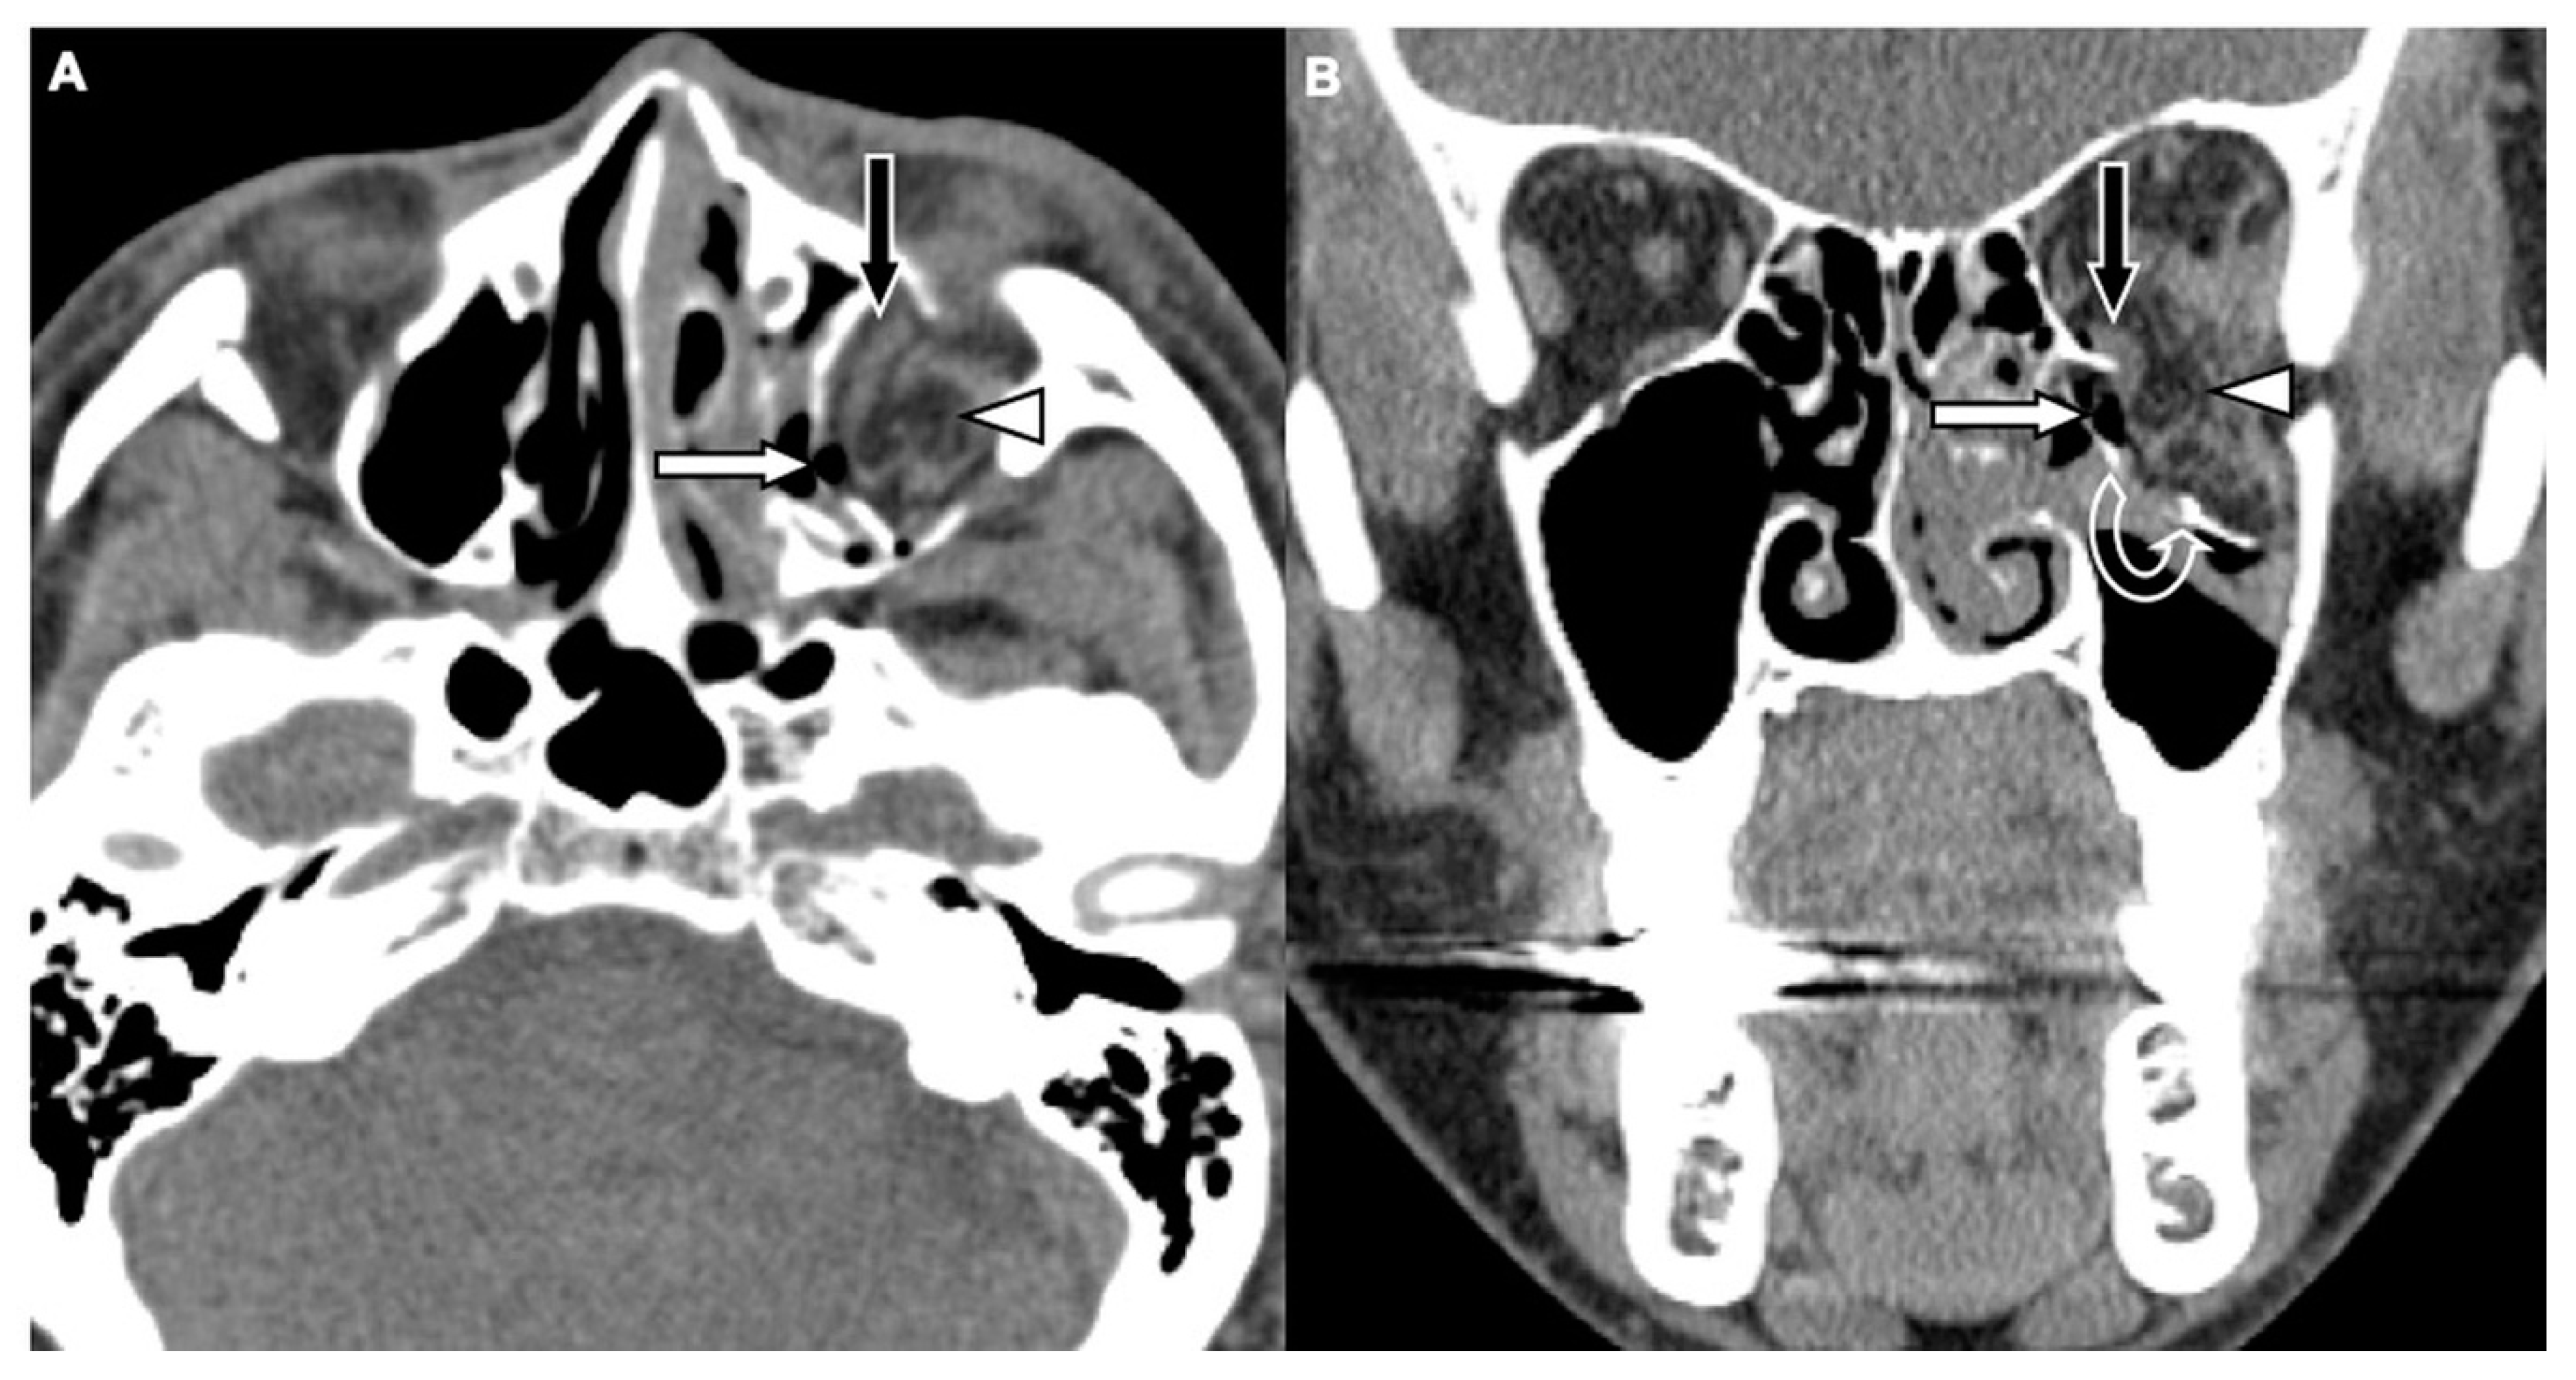

Figure 1. CT images of a 29-year-old male with assault-related head trauma and a concomitant left orbital floor fracture (OFF). An axial head CT image (A) and the corresponding coronal facial CT image (B) show gas bubbles (black arrow) entrapped between the discontinuous floor fragments (white arrows). Left type 2 maxillary hemosinus (MHS) (arrowhead) and a left zygomatic fracture are also noted in (A).

Two board-licensed radiologists (L.D.J. and Y.Y.C.) who were blinded to the patients’ clinical information reviewed only the head CT images by means of consensus. The radiologists were permitted to manipulate the window and level of the images. The CT variables related to the cranium included intracranial hemorrhage (ICH; epidural hemorrhage, subdural hemorrhage, subarachnoid hemorrhage, and intracerebral hemorrhage), and skull fractures. The CT variables related to OFFs included orbital floor discontinuity (Figure 1), gas bubbles entrapped between the floor fragments (Figure 1), inferior extraconal emphysema (Figure 2), orbital fat herniation into the maxillary sinus (Figure 2), and ipsilateral maxillary hemosinus (MHS, Figure 3). MHS was defined as high-attenuation opacity at the dependent portion of the maxillary sinus measuring ≥ 45 Hounsfield units (HU) as the lower limit of attenuation for clotted blood [15]. Since MHS is a relevant indicator used to detect OFFs on CT scans [5,16], we further classified MHS into the following three CT subtypes: (1) Type 1, high-attenuation opacity mixed with mottled gas (Figure 3A); (2) Type 2, air–fluid level (Figure 3B); and (3) Type 3, full opacification of the sinus (Figure 3C).